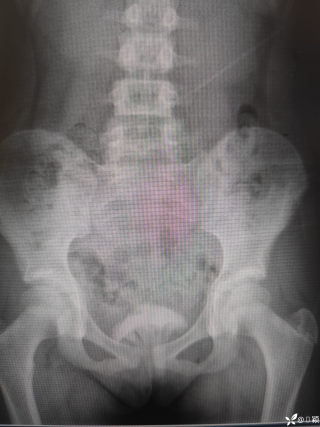

2023年10月26日,来自山东菏泽市成武县的小烨和他家人的命运被彻底改变了。这个原本阳光、可爱的小男孩在一次意外被撞击后,在医院检查出了腹腔内存在肿瘤,并在手术中被切除了包括十二指肠、胰腺、大部分胃和小肠等多个器官。此后便无法再像正常人一样吃饭、喝水,活着要靠长期静脉注射营养液。一份2024年12月由第三方机构出具的司法鉴定意见书显示,当时给小烨做手术的成武县人民医院在该医疗行为中存在过错,与小烨的损害后果之间存在因果关系,建议医疗过错在损害后果中的原因力大小为同等原因。此外,另一份由成武县卫生健康局在2025年9月28日发出的书面答复中显示,成武县人民医院存在24小时内未完成病历;手术知情